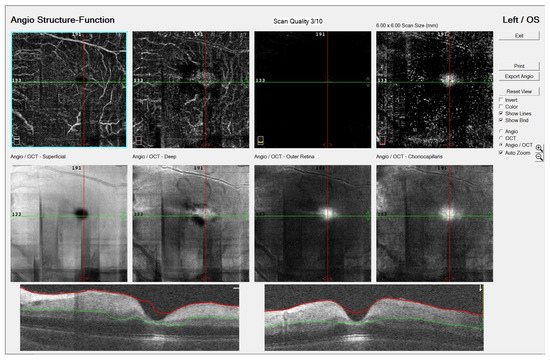

Central Retinal Artery Occlusion in a 6-Year-Old Child with an Acute Chickenpox Infection: A Case Report

by Dunja Bajtl, Tvrtka Benašić, Jelena Petrinović-Dorešić, Nenad Vukojević, Dubravka Biuk, Ivona Barać and Sanja Perić

J. Clin. Med. 2025, 14(24), 8685; https://doi.org/10.3390/jcm14248685 - 8 Dec 2025

Background: Central retinal artery occlusion (CRAO) is an ophthalmic emergency attributed to a vessel occlusion with an embolus or a thrombus and may occur during the hypercoagulable state, inflammation, or vasculitis. CRAO may occur in children; however its incidence is very rare. Most [...] Read more.

Background: Central retinal artery occlusion (CRAO) is an ophthalmic emergency attributed to a vessel occlusion with an embolus or a thrombus and may occur during the hypercoagulable state, inflammation, or vasculitis. CRAO may occur in children; however its incidence is very rare. Most pediatric cases have detectable etiologies. Case Presentation: We describe the case of an otherwise-healthy six-year-old female, who presented with the sudden and complete vision loss of the left eye lasting over twelve hours after a six-day chickenpox exanthema, followed by a high fever. All the ophthalmological, laboratory, and instrumental investigations led to the diagnosis of a left CRAO. Laboratory testing was unremarkable except for the transient elevation of D dimers (1363 µg/L), IgM anticardiolipin antibodies (238.5 CU), and IgG anti-beta-2 glycoprotein-1 antibodies (76.1 CU) on admission. Thrombolytic treatment was not exerted because of late presentation to the hospital. Treatment with steroids, antiviral medications, antibiotics, and anticoagulants was obtained, but the visual outcome was poor during the hospitalization and at the last follow-up. We could not ascribe features of this case to any etiological condition apart from the documented ongoing chickenpox infection. Conclusions: This is the first case report of CRAO in a child with transient aPL elevation and acute chickenpox infection. Full article

(This article belongs to the Section Ophthalmology)

Show Figures

Figure 1